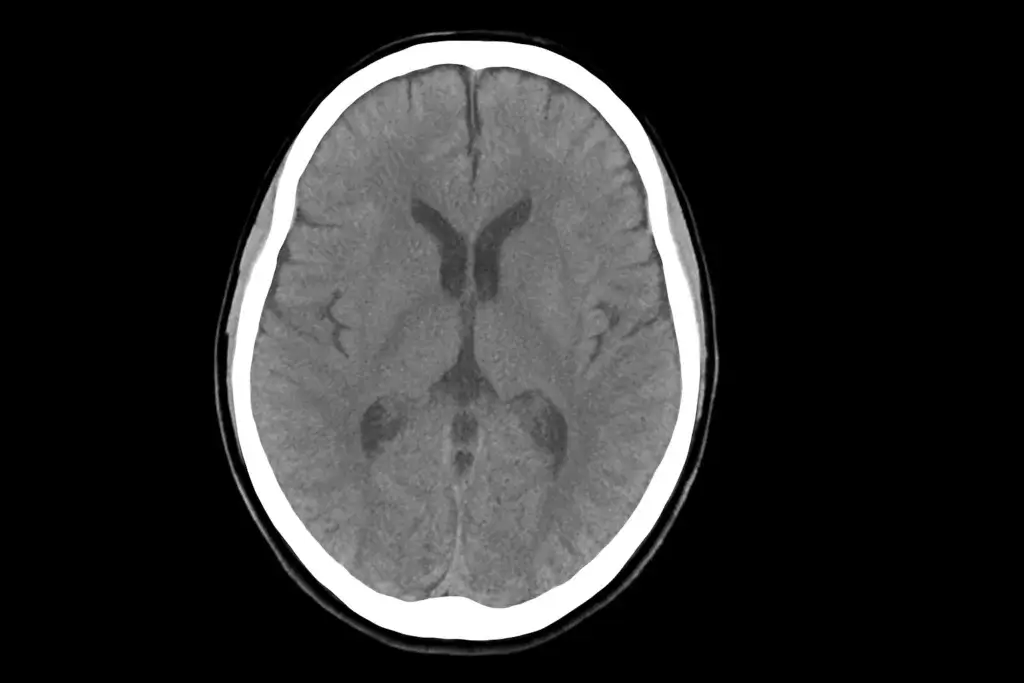

FDA aprova Modeyso para glioma difuso de linha média com mutação H3 K27M

Em 6 de agosto, a Food and Drug Administration (FDA) aprovou, sob processo acelerado, o uso de Modeyso (dordaviprone) para adultos e crianças a partir de um ano de idade com glioma difuso de linha média com mutação H3 K27M e doença progressiva após pelo menos uma linha de tratamento prévia. A decisão marca um […]